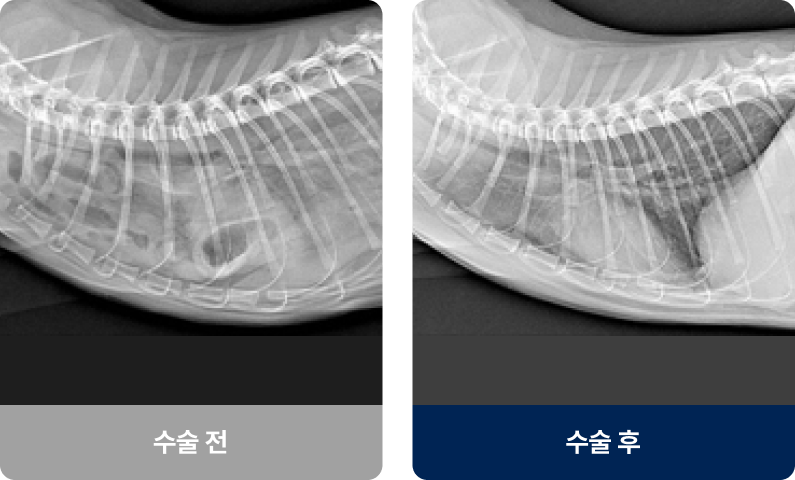

횡격막(가슴과 배를 구분하는 근육)에 구멍이 생겨, 간·위·장기 같은 복부 장기가 흉강 안으로 들어간 상태로, 이는 폐를 압박하고 폐가 완전히 팽창하지 못하게 하여 호흡 곤란을 유발합니다. 주로 교통사고나 낙상 등의 외부 충격으로 발생하며 호흡곤란, 구토, 식욕 저하 증상을 보입니다.